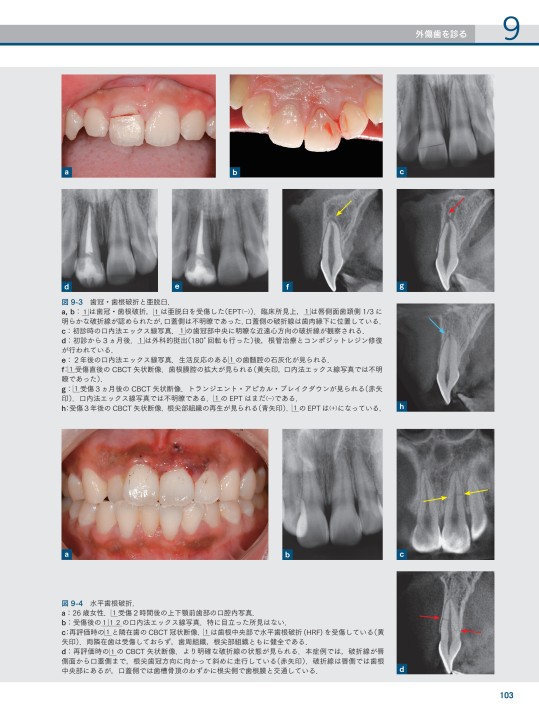

歯科用コーンビームCT徹底活用ガイド - クインテッセンス出版。CBCT(コーンビームCT)について|さとうデンタルクリニック - YouTube。歯内療法成功のためのコーンビームCT活用法。スキャンするために裁断したものです。基礎から学ぶデジタル時代の矯正入門 : IOSと3Dプリンターを応用したカスタ…。ご注意下さい。PEARS 小児救急評価・認識・病態安定化 PEARSプロバイダー。袋に梱包しております。理学療法 作業療法国家試験整形外科運動療法ナビゲーション2冊セット 上下肢・体幹。お値引き後の価格はこちらから提示させて頂きます。図説 神経機能解剖テキスト。また、過剰なお値引きはご遠慮願います。外傷初期診療ガイドラインJATEC 改訂第6版。返品はご容赦ください。精神病水準の不安と庇護 ウィニコットとの精神分析の記録(岩崎学術出版社)。。歯内療法成功のためのコーンビームCT活用法。※背表紙を切断していますので、普通の本のようには読めません。全てのページが一枚一枚バラバラになっております。99 内科学 第12版。インプラント治療はチームアプローチ : 検査・診断・手術・コンサルテーション。裁断しているため、「全体的に状態が悪い」にしてあります。書き込みは見落としがあるかもしれませんが読む分には問題なく綺麗な状態です。視能学第3版【Textbook of Orthoptics】。誰にでもできる咬合採得。まとめ売りで送料分お値引きさせて頂きますので、ご希望の場合はコメントをお願いいたします。多数(冊)ご購入の場合は大幅にお値引きさせて頂きます。改訂第6版 救急診療指針 上巻。【新品・コード未使用】イヤーノート2026。※仕事の都合上返信のお時間があまり取れません。単品でのお値引きを希望する場合のコメントは受け付けておりません。犬と猫の臨床外科 - 渡邉一弘著 - EDUWARD Press。健康・医学 Textbook of Endocrinology 14th Ed。その場合のコメントは削除またはスルーさせて頂きますのでご了承下さい。即決購入可能です。上達の法則 効率のよい努力を科学する。靈氣と仁術富田流手あて療法 富田魁二著 復刻書。歯内療法におけるコーンビームCTの活用法を詳述した専門書。- タイトル: コーンビームCT活用術- 著者: Shanon Patel, Simon Harvey, Hagay Shemesh, Conor Durack- 出版社: クインテッセンス出版- ISBN: 9784871205996ご覧いただきありがとうございます。現代数理論理学序説